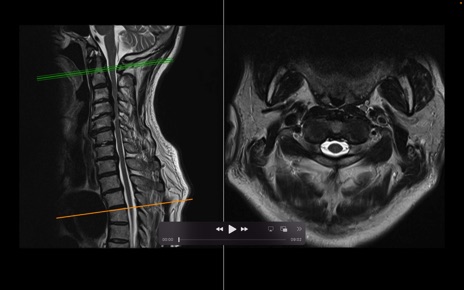

頚椎MRI

T2WI(横断像)

T2WI(矢状断像)